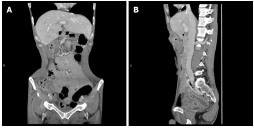

回顾既往病史,患者于2014年出现反复腹泻和腹胀,被诊断为CD。确诊后,接受了对症治疗。2017年,由于腹痛和肠梗阻症状急性加重,进行了横向结肠造口术,有效缓解了患者的症状。后来,患者接受了美沙拉秦治疗,但反应不佳。对比增强CT未观察到肿瘤发生(图1)。因此,2018年开始接受英夫利昔单抗诱导治疗(第1周、第2周和第6周静脉滴注5mg/kg,此后每8周一次)。10个月后,患者因横结肠造口进行性挛缩而返回医院。患者除海鲜过敏外,无特殊病史。无吸烟史,家族癌症史阴性。

图1. 腹部增强计算机断层扫描图像